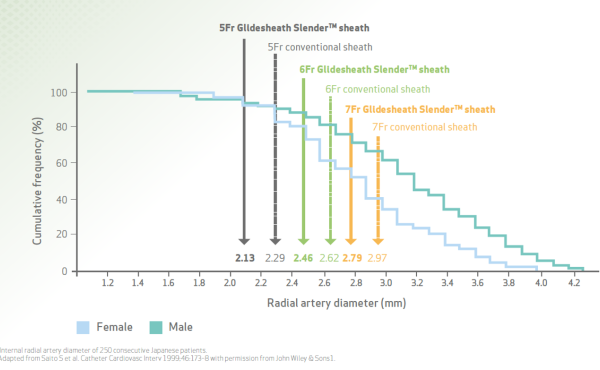

- Can you explain the relationship between the sheath size and vessel diameter?

- Sure! The graph below sheds light on the relationship between the two. You can determine vessel size using ultrasound, which, according to some data, can also improve puncture success rate.

If ultrasound is not an option, using contrast and fluoroscopy is a viable alternative.